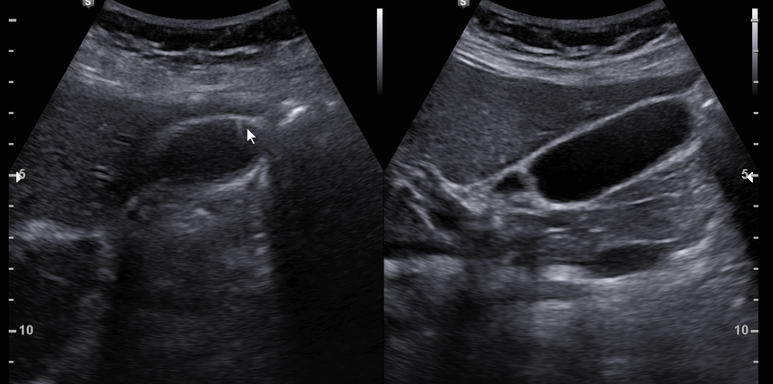

투약 두달 시점에 초음파 시행; 모래양 담석/담낭오니는 관찰되지 않는다.